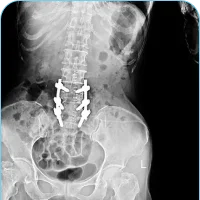

Back Pain Diagnosis

Our Approach To Non-Surgical Back Pain Treatment